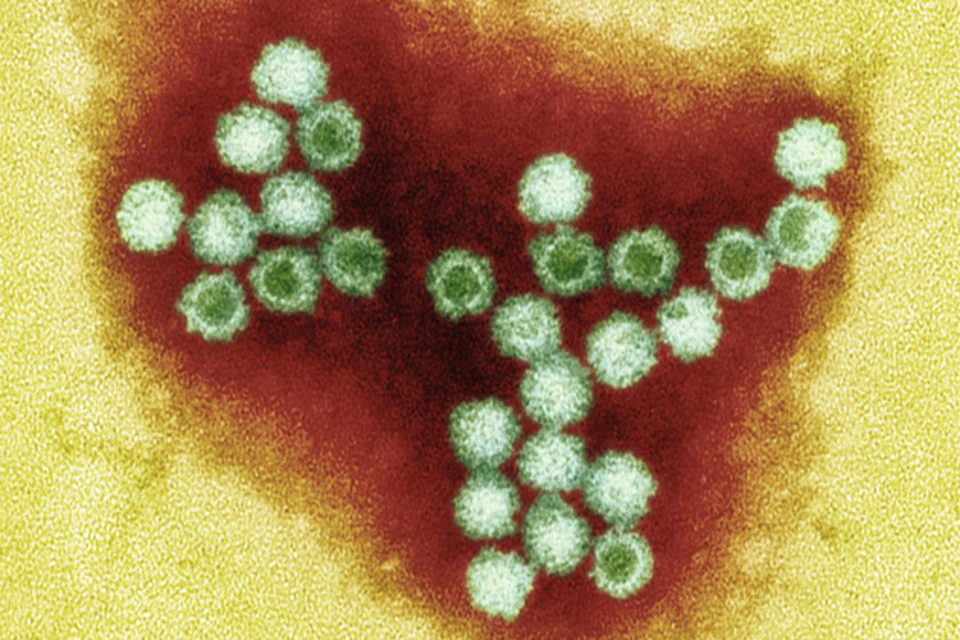

Медицинские снимки и изображения опоясывающего герпес вируса

Раздел: Фотодневник открытий